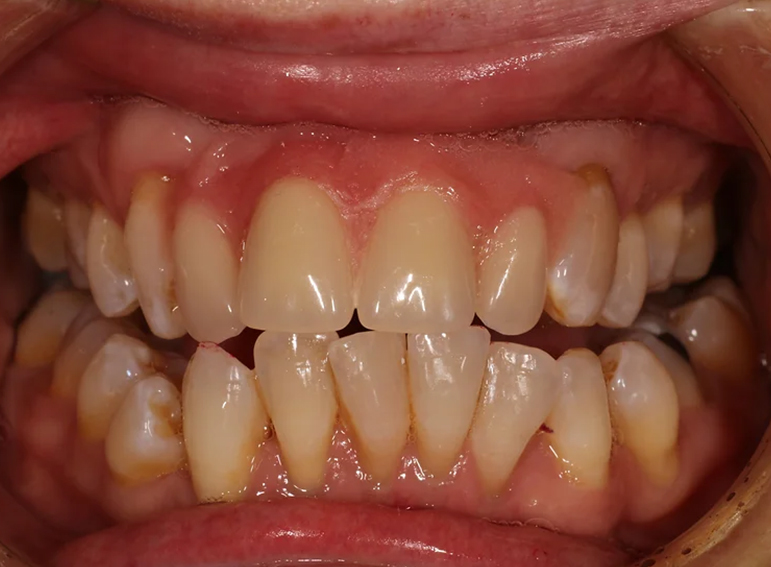

Oral rehabilitation after a road traffic accident.